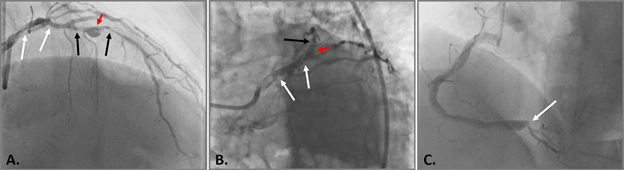

Figure 1 Selective coronary angiography.

A. and B. 80% calcified stenosis in the terminal LCA and proximal LAD segment (white arrows), 90% calcified stenosis in the middle LAD segment (black arrows) and aneurysm in the middle LAD segment with a diameter of up to 6 mm (red arrow); C. RCA is diffusely changed, expanded throughout up to 5-6 mm; VZV is occluded from the orifice (white arrow).